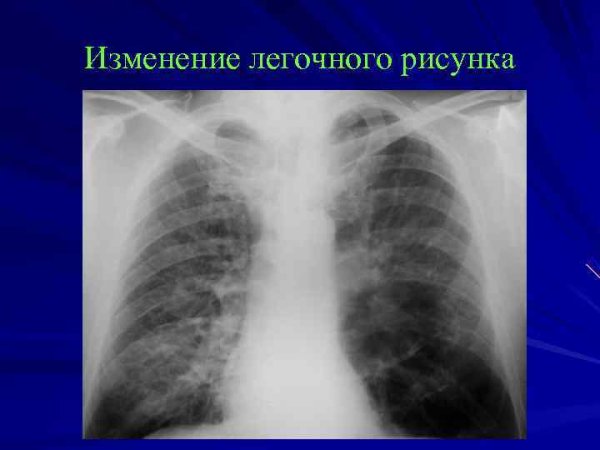

Изменение легочного рисунка – это понятие, которое относится к обнаружению и оценке изменений в структуре и паттерне легких на медицинских изображениях, таких как рентгеновские снимки или компьютерная томография. Легочный рисунок отражает состояние и функциональность легких, и его изменения могут быть связаны с различными заболеваниями и патологиями. Наблюдение и анализ изменений легочного рисунка помогает в диагностике и контроле этих состояний, что является важным инструментом в клинической практике. Детектирование и интерпретация этих изменений проводится специалистами радиологии и пульмонологии с использованием специального программного обеспечения для медицинского изображения. Все это позволяет более точно определить причину и характер изменений в легочном рисунке, а также вовремя начать необходимое лечение и наблюдение за пациентом.